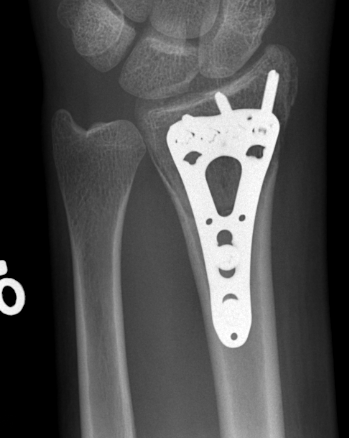

![]() |